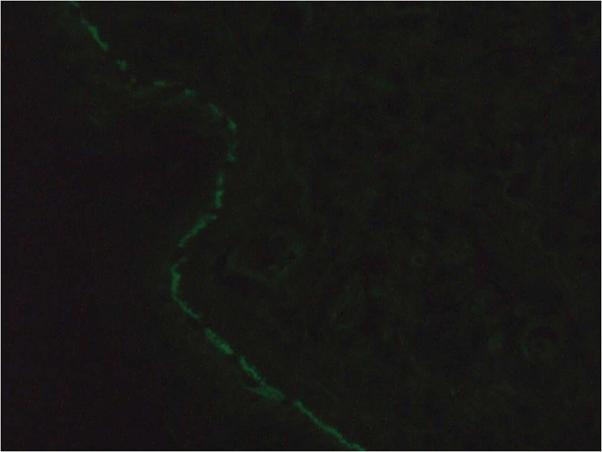

Maalouf Nadine S, Hanna Dominique

Université de Sherbrooke, Sherbrooke, QC, Canada.

JAAD Case Rep. 2019 Oct 24;5(11):966-969. doi: 10.1016/j.jdcr.2019.08.019. eCollection 2019 Nov.